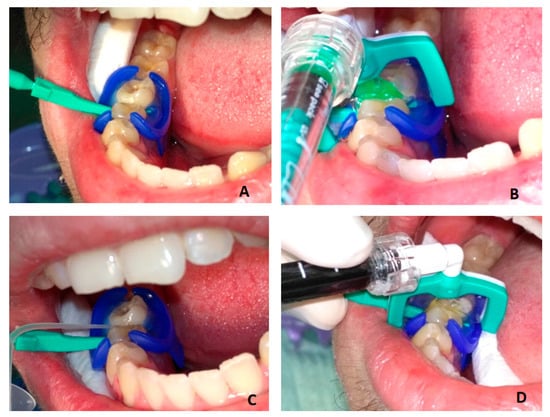

Figure 5 demonstrates the bitewing radiographs of a patient before treatment and one year after treatment. Infiltrated lesions have been arrested, while remineralized and control lesions have progressed (Figure 5).

Figure 5. Bitewing radiographs before (a) and 1 year after treatment (b). Arrows indicate the initial proximal caries lesions and their condition at the 1-year follow-up. Tooth 16 mesially (caries D1)—infiltrated and arrested after 1 year. Tooth 25 distally (caries reaching DEJ)—remineralization, progressed after 1 year to caries D1. Tooth 24 distally (caries D1)—control (no treatment) progressed after 1 year to caries D2. E2 is caries reaching the inner half of enamel, D1 is caries reaching the outer third of dentin, and D2 is caries reaching the middle third of dentin.